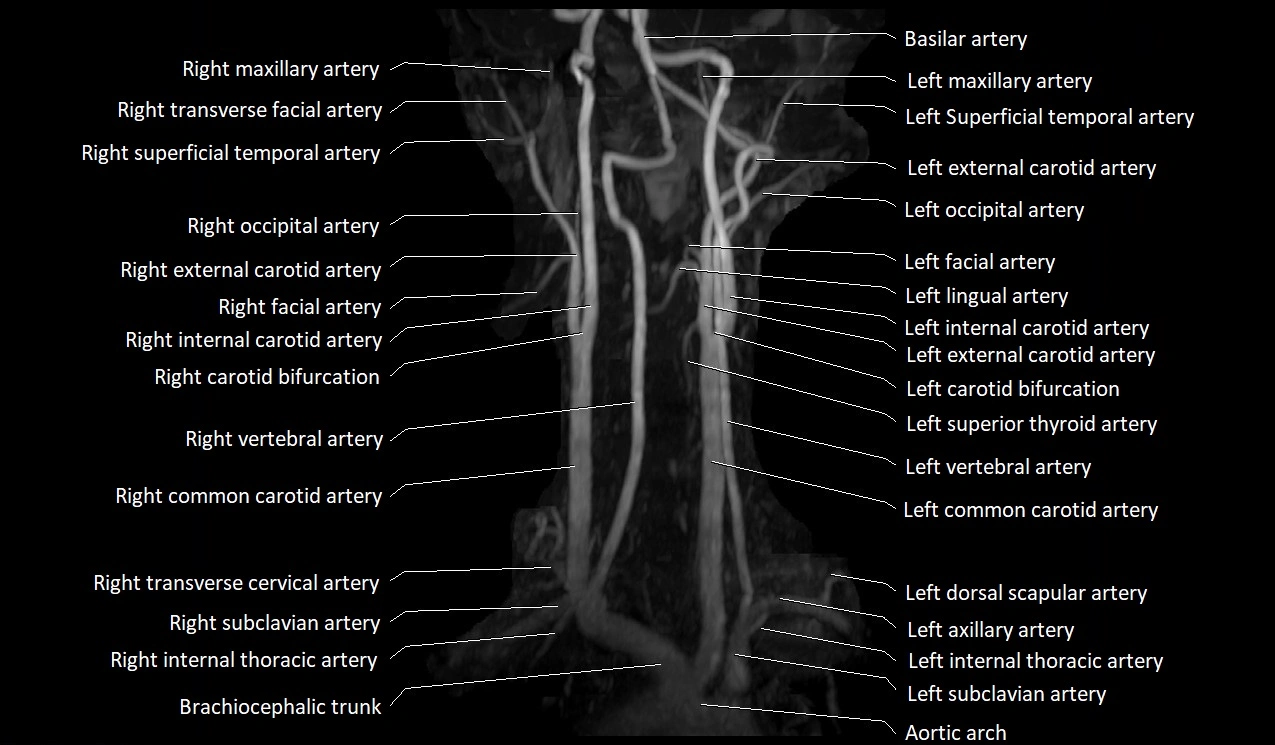

MRI images

image